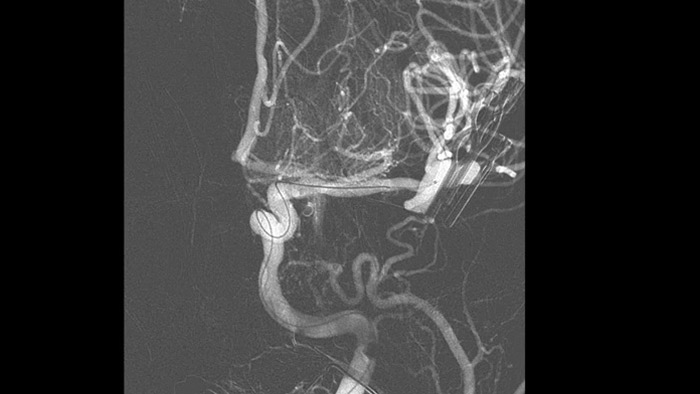

Ver con claridad y navegar de manera eficiente cuando se tratan los aneurismas cerebrales

Los nuevos dispositivos pueden ser difíciles de visualizar cuando se tratan aneurismas cerebrales, lo que puede alargar el tiempo del procedimiento. Eso hace que las excelentes imágenes 2D y 3D sean más importantes que nunca para guiar las decisiones de tratamiento y la colocación del dispositivo, y administrar la dosis de radiación de manera eficiente.

Navegue con precisión utilizando la guía de imágenes 3D dinámicas

Visualización mejorada de SmartCT Roadmap

SmartCT Roadmap mejora la visualización de vasos superpuestos para apoyar la navegación precisa de la aguja guía y el catéter a través de vasculatura compleja. Ofrece precisión de alto nivel con compensación en tiempo real para los movimientos del gantry, de la mesa y los pequeños movimientos del paciente.